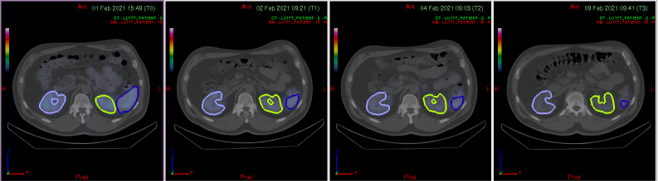

Dosimetrie-Visual

© Oncosia Scientific GmbH